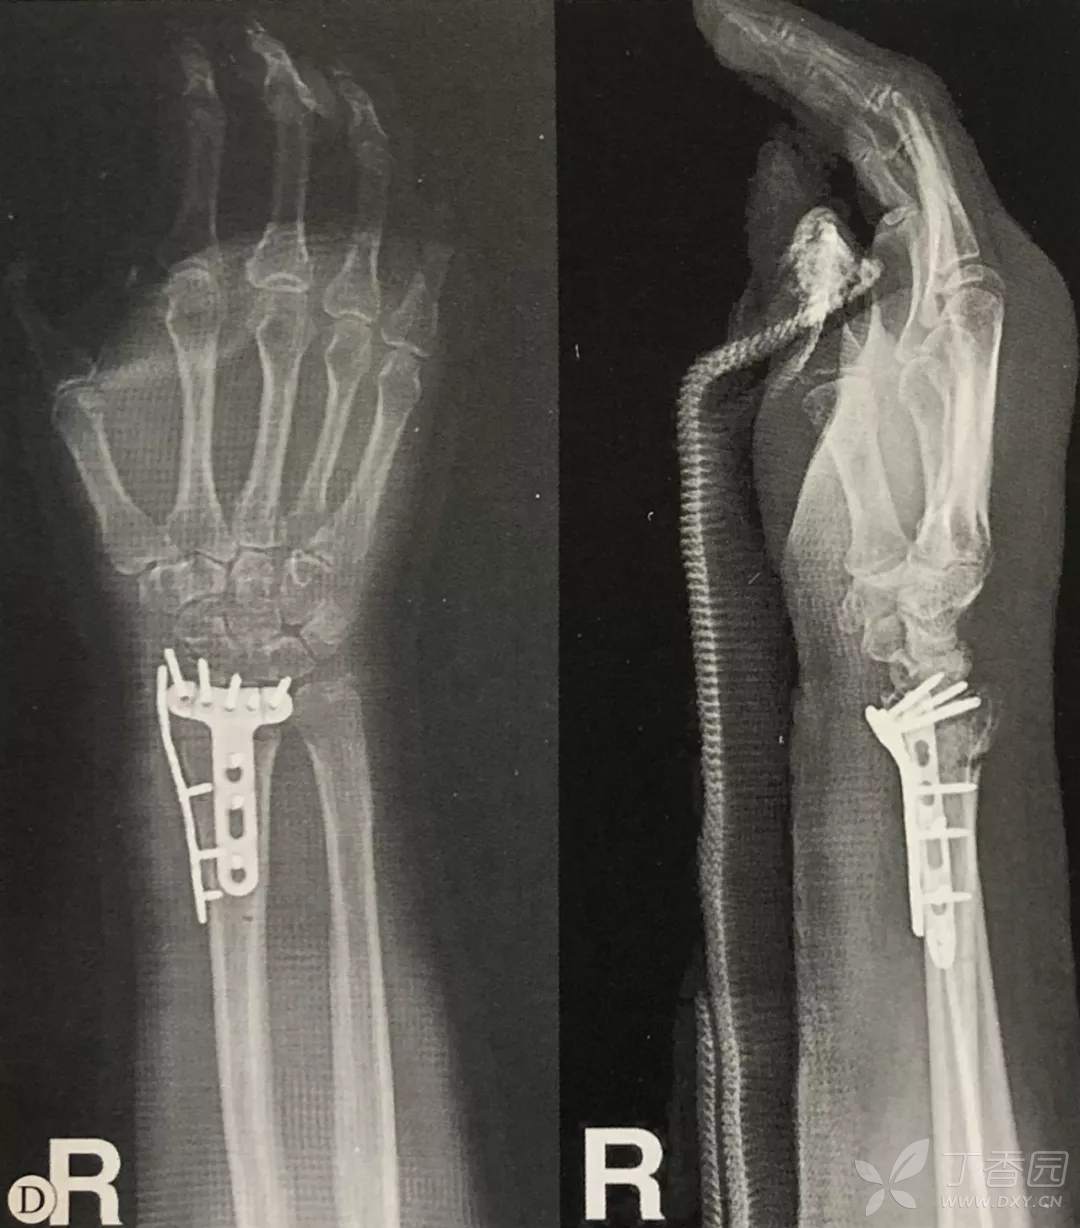

- 采取前述方法复位后,应用锁定钢板进行固定;

- 钢板应尽量靠近关节面放置,以使远端螺钉位于软骨下骨内,提供良好的力学支撑,对于骨质疏松患者,这点尤为重要;

- 部分解剖锁定钢板设计了桡骨茎突螺钉,通过该螺钉可以固定桡侧柱和桡骨茎突骨块;

- 第三代桡骨远端解剖型锁定钢板允许在一定角度范围内置入锁定螺钉,也可通过向桡骨茎突方向置入螺钉固定桡侧柱和桡骨茎突骨块。

对于大多数骨块,将钢板尽量靠近关节面放置,可以使螺钉通过掌侧唇固定;

桡侧钢板远端螺钉位置:

McQueen等的研究表明,桡骨远端背侧皮质较薄,而关节面下的软骨较为致密,因此钢板应贴近桡骨远端从而使螺钉向背侧远端,使螺钉固定于软骨下骨而非置于背侧皮质。